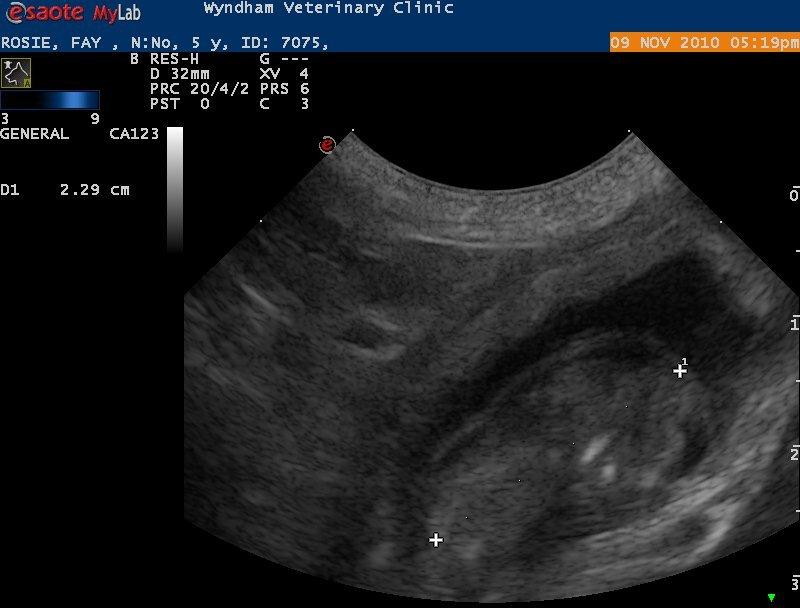

SBT101 Posted November 5, 2010 Share Posted November 5, 2010 Thankyou and yes it will be a very busy christmas ;) We did see another puppy that didn't look right and is possible being obsorbed ;) I nearly cried on the spot, the poor little darling. I am currently waiting for the vet to ring back so I can possible take Cynda back in and get her progestrone levels checked. She has been quite herself for a while but I was putting it down to hormonal changes. Here are the scans from today...Aren't they just gorgeous Link to comment Share on other sites More sharing options...

Puglodge Posted November 9, 2010 Share Posted November 9, 2010 (edited) We have 3 puppies confirmed with an ultrasound this afternoon. The countdown is on for all of us. Edited November 11, 2010 by Puglodge Link to comment Share on other sites More sharing options...